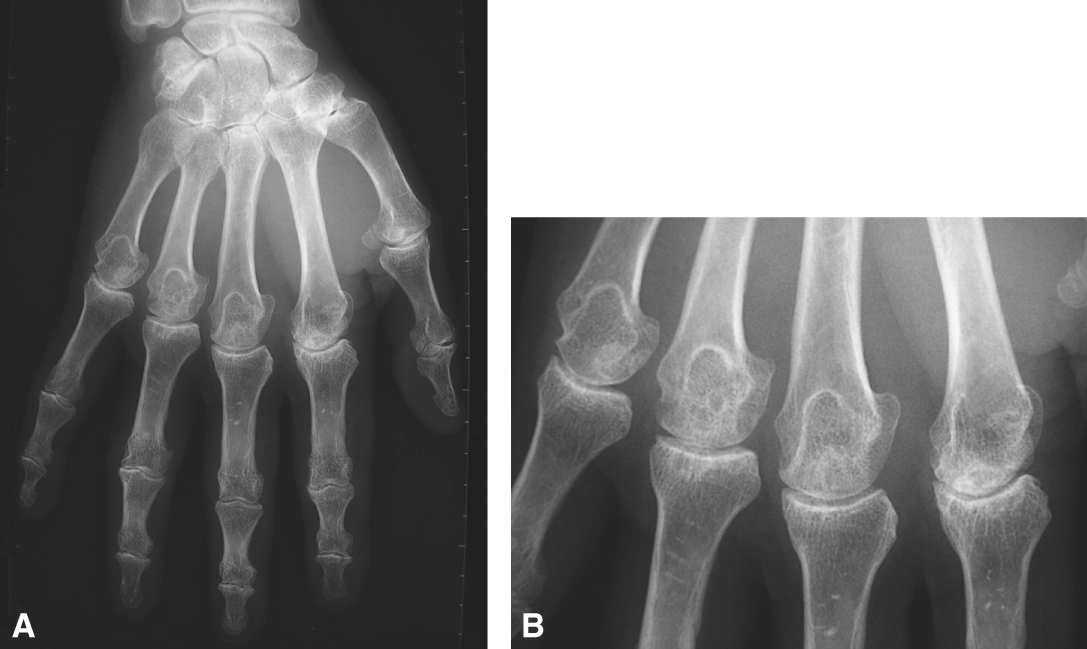

Fig. 24.1.

Hémochromatose.

Arthropathie des articulations métacarpophalangiennes d'allure mixte, destructrice (pincement de l'interligne articulaire et géodes sous-chondrales) et constructrice (condensation osseuse et ostéophytose périphérique). A. Radiographie de la main de face. B. Cliché centré sur les articulations métacarpophalangiennes.

- Les signes les plus caractéristiques concernent tout particulièrement l'atteinte des MCP 2 et 3 : ostéophyte très particulier en " hameçon " au niveau de la tête métacarpienne, pincement articulaire.

- Signes d'arthropathie chondrale et sous-chondrale sur des articulations peu touchées par l'arthrose, avec des géodes cerclées par une condensation et disposées en " chapelet " dans la zone osseuse sous-chondrale, des ostéophytes à extrémité arrondie.

- Chondrocalcinose articulaire (fig. 24.1).